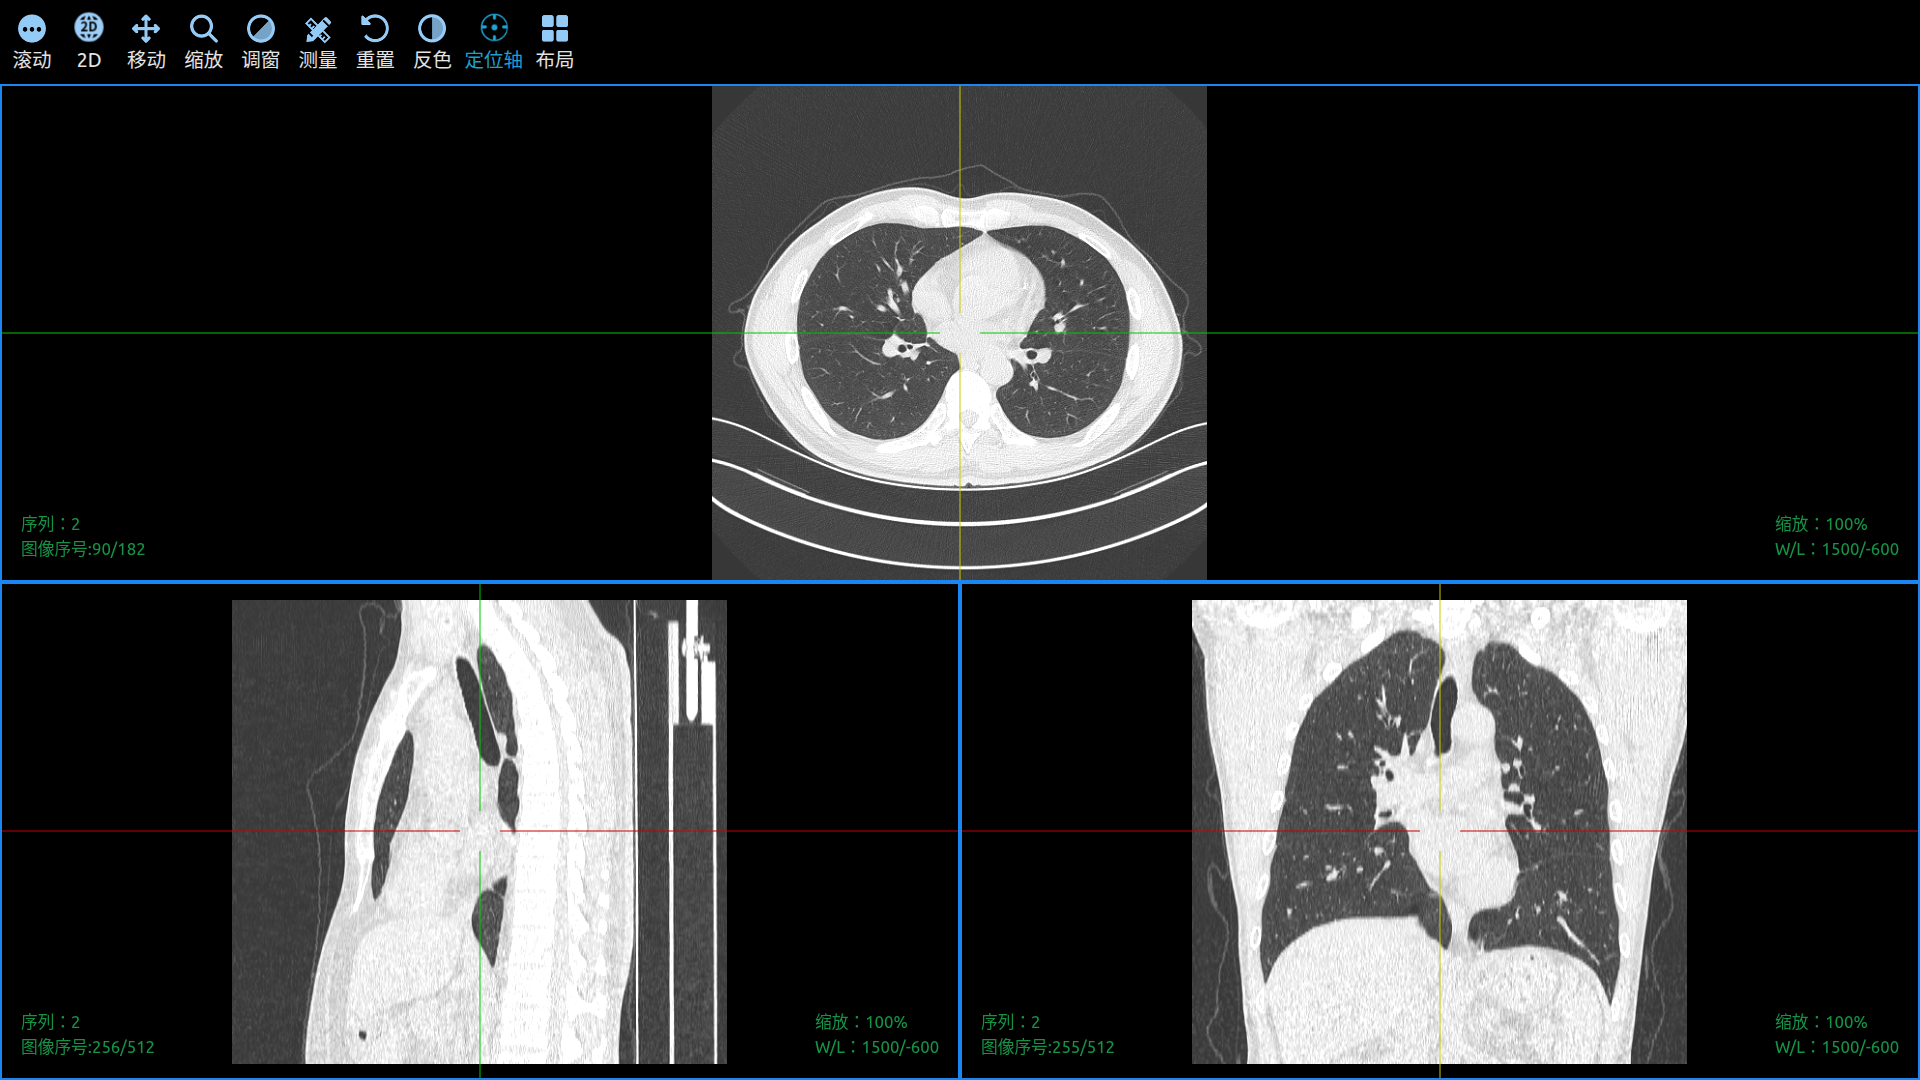

Use Cornerstone3D to View DICOM Images in a Web Browser.